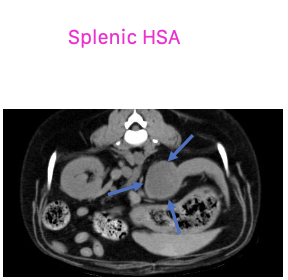

what are the common primary visceral sites of hemangiosarcoma?

-spleen is the most common location

-liver

-other: kidney, retroperitoneal space, nasal cavity, oral cavity, bone

what will be seen on abdominal radiographs in patients with hemangiosarcoma?

nonspecific: mass

loss of serosal detail

what is the appearance of hemangiosarcoma lesions in the abdomen using abdominal ultrasound?

-heterogenous (hypoechoic to targetoid to mixed)

-cavitation

- +/- peritoneal effusion